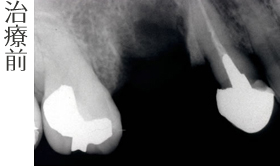

インプラント治療の前に(骨の環境整備)右上小臼歯部

右上の1番は抜歯となりました。 抜歯後に骨造成(GBR)を行います。

- 骨造成(GBR)